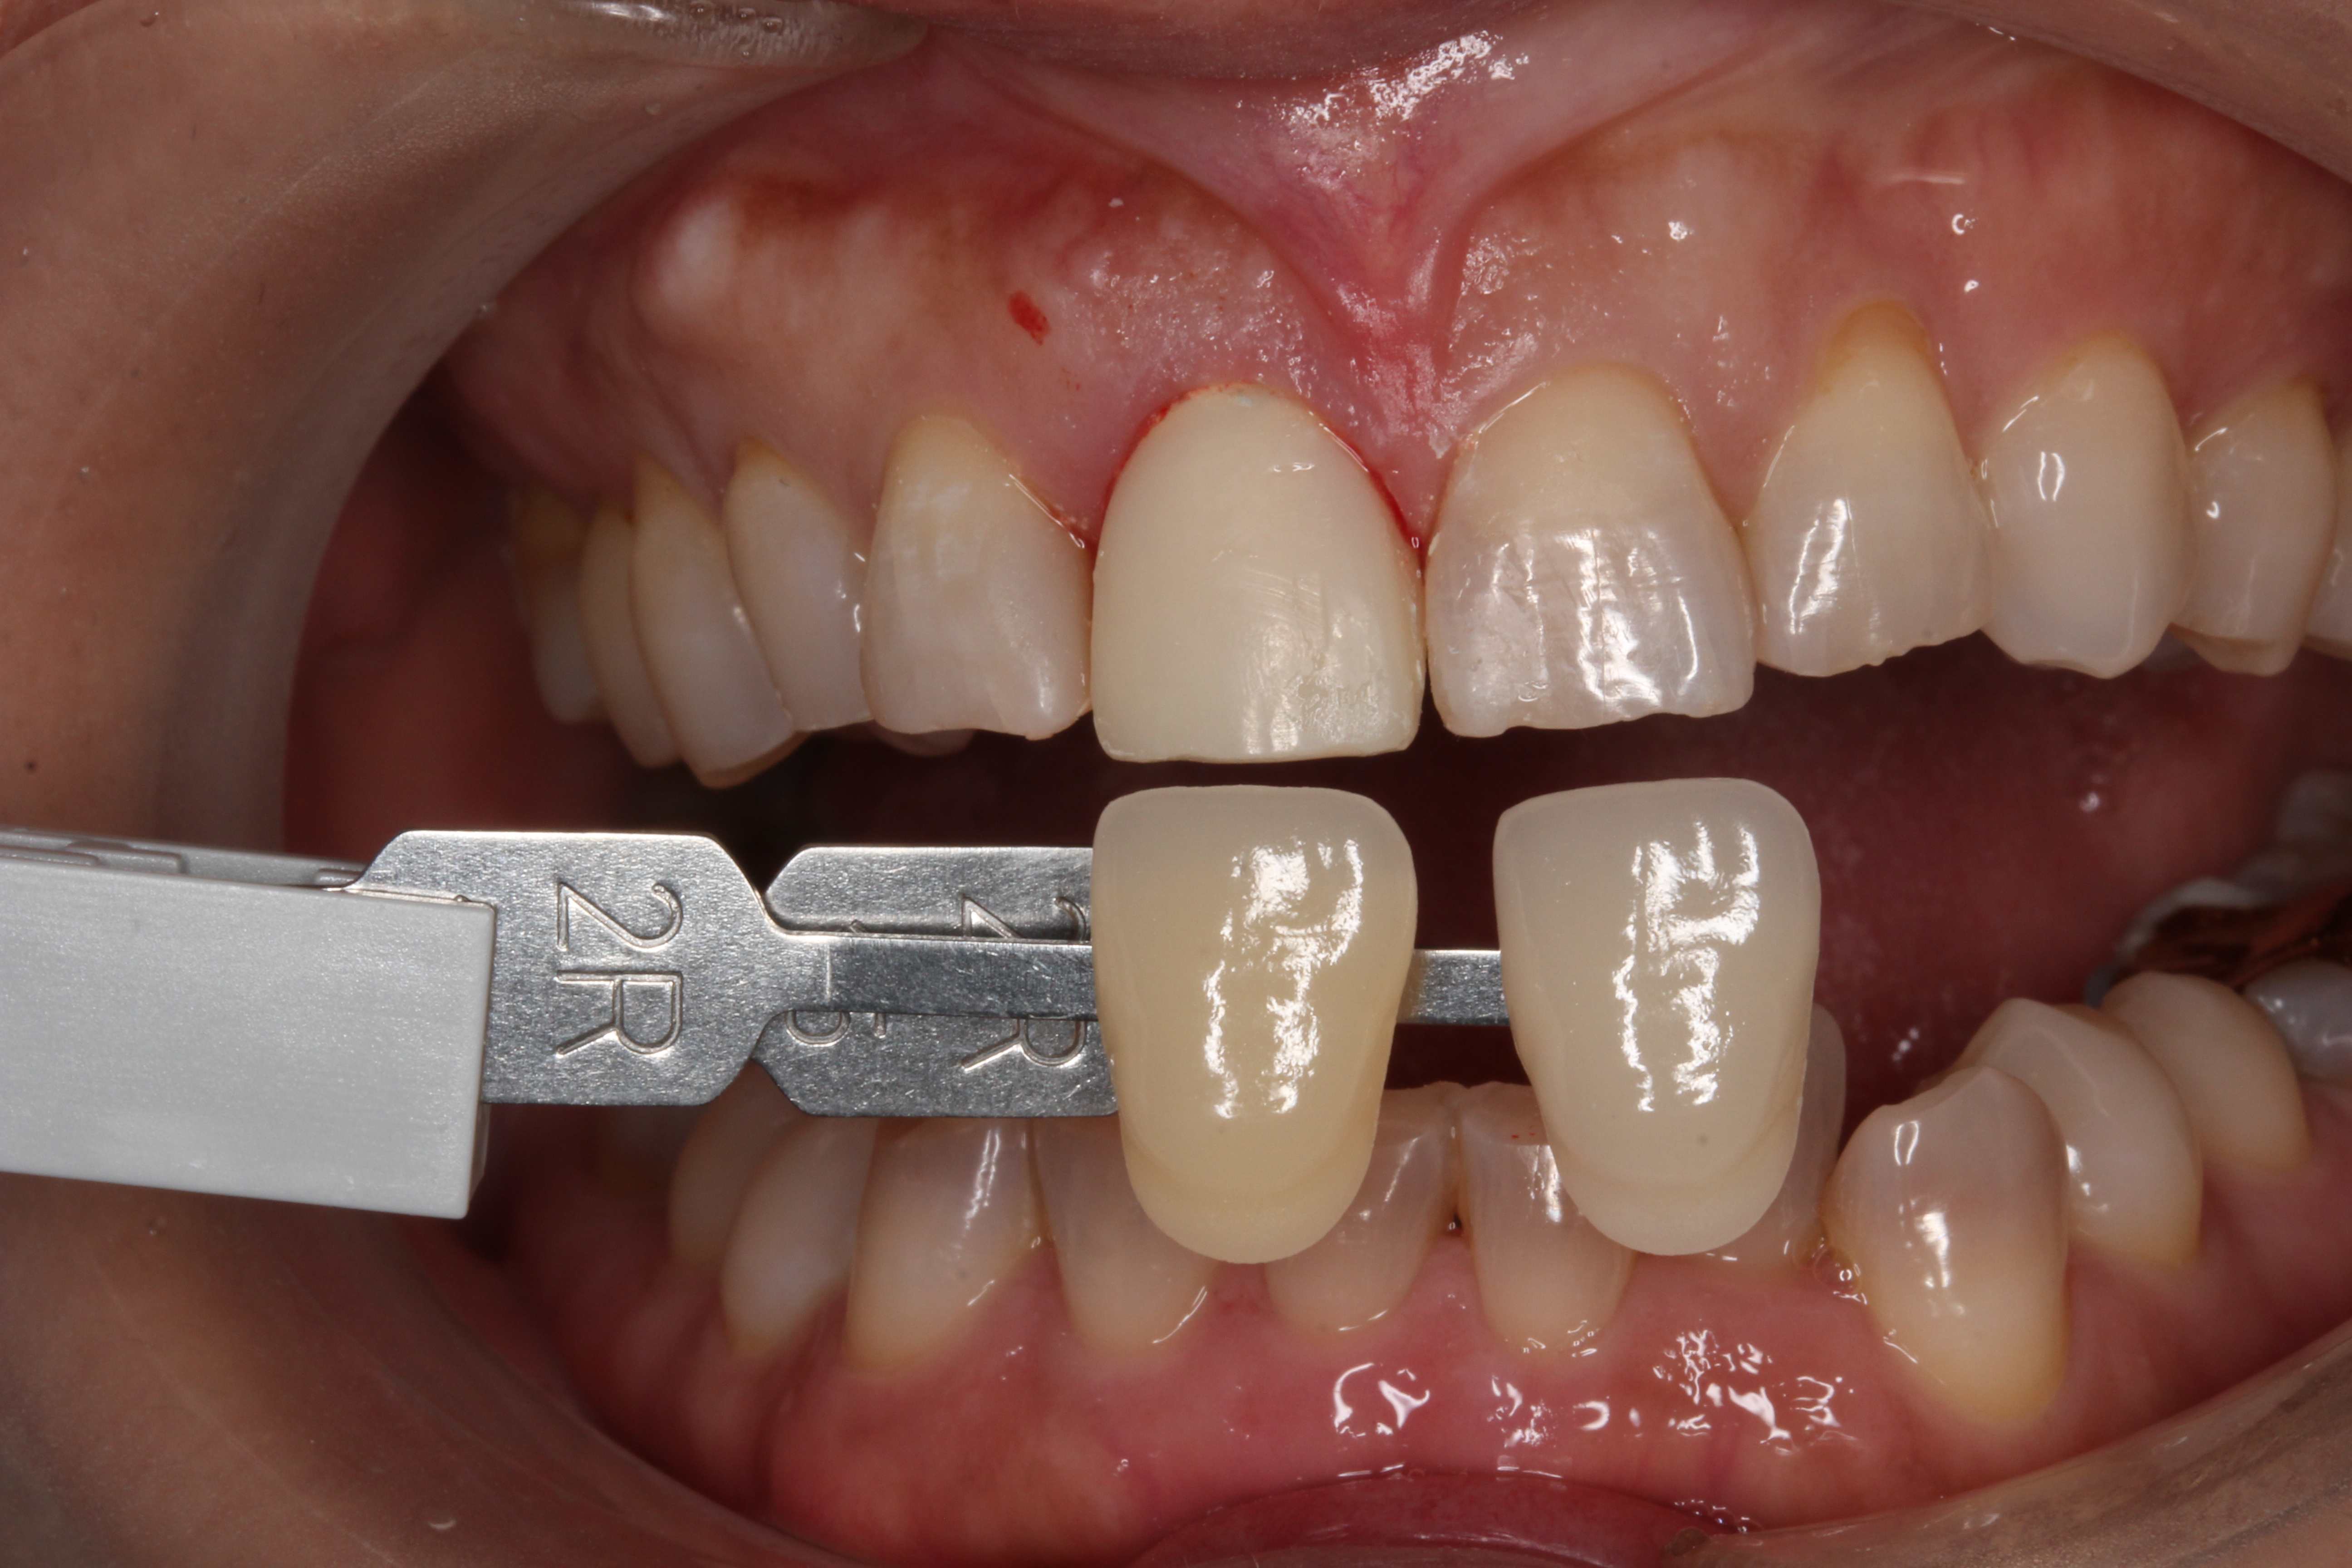

前歯で大切なのは歯の色合いです。

全ての人が違う歯の色・形をしています。指紋と一緒で同じ人はいません。

こだわりを持って色形を再現する場合は担当する歯科医師の技量はもちろん、

シェードテイキングという色の記録と、

製作する歯科技工士の職人技が必要となってきます。

様々な色の見本を当てがって、その方の歯の色を決めていきます。

また歯科技工士が直接、患者さんの歯の色を確認し、患者さんの希望を聞きながら色をチェックします。